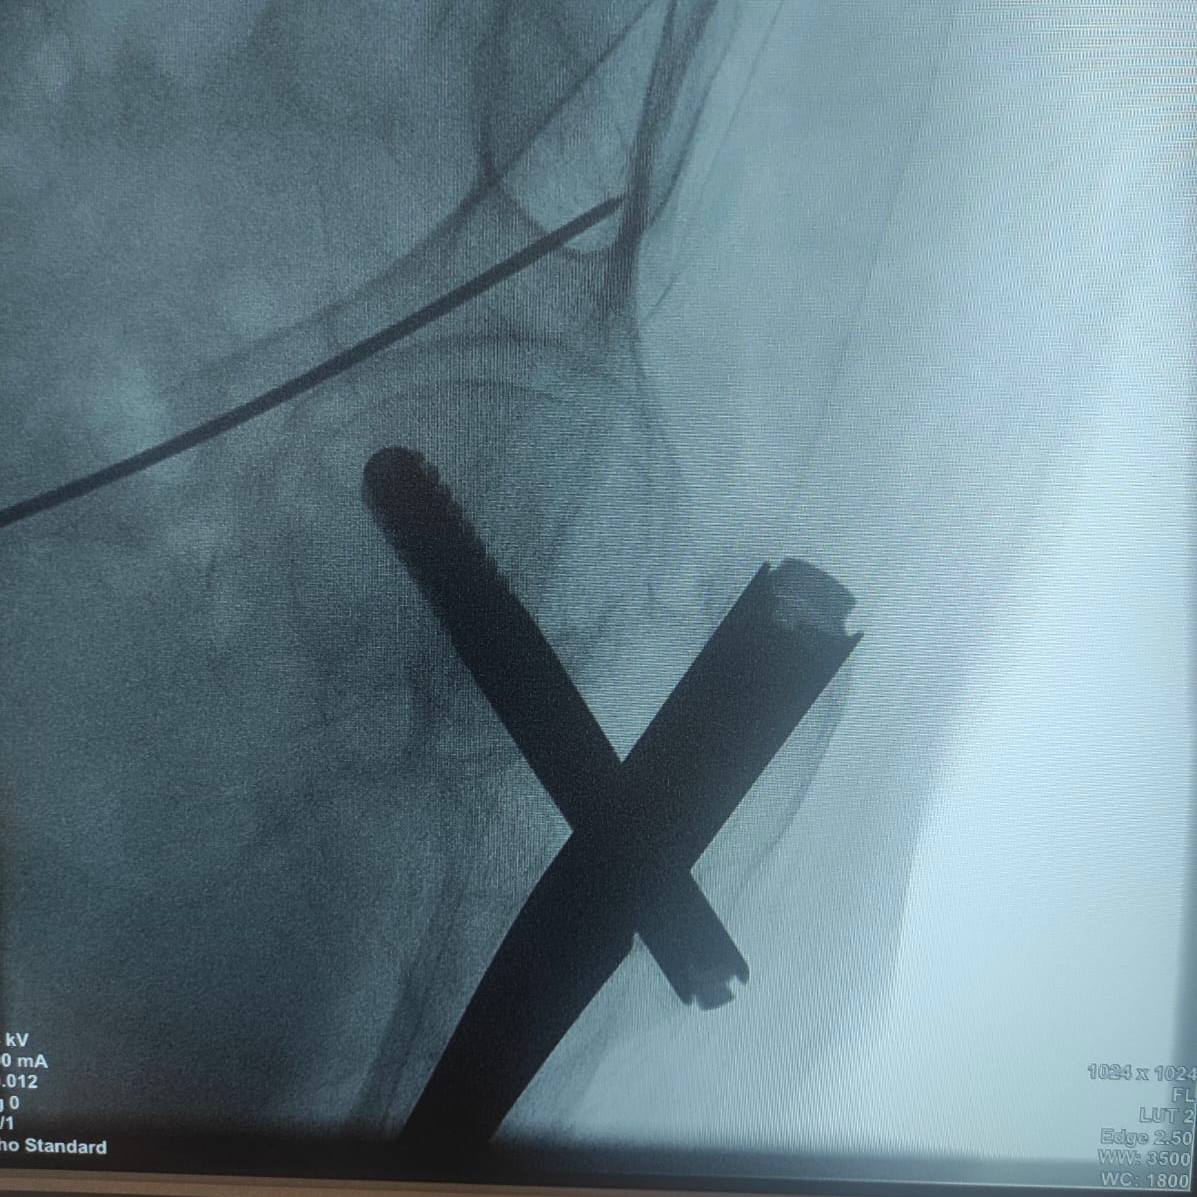

Была выбрана методика перкутанного остеосинтеза винтами. Операция ранее не проводилась в больнице, поэтому методика была продемонстрирована руководителем Клиники реконструктивно-восстановительной хирургии повреждений конечностей и таза, д.м.н. Алексеем Гринь.

Методика была разработана Никитой Заднепровским, к.м.н., научным сотрудником, врачом травматологом-ортопедом отделения сочетанной и множественной травмы ГБУЗ «НИИ СП Н. В. Склифосовского ДЗМ». Операция проводилась через минимальные разрезы.